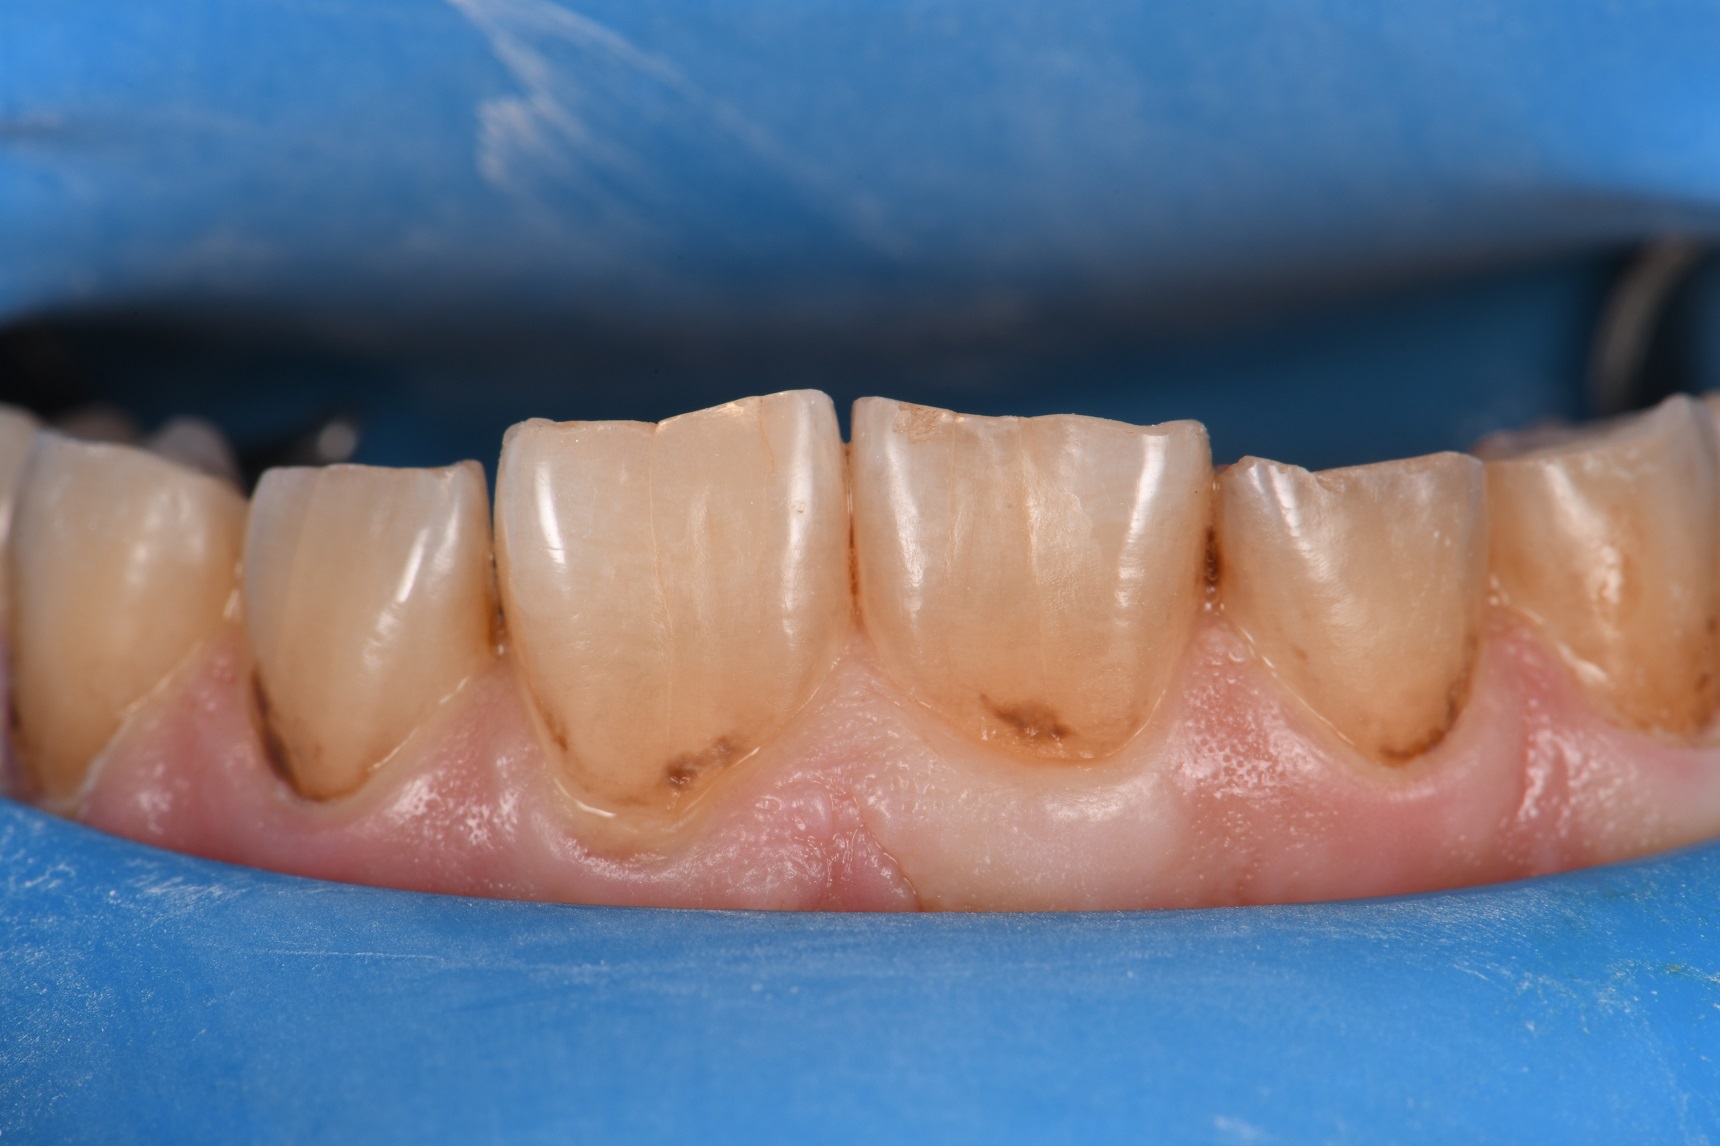

From www.styleitaliano.org

Full quadrant restoration Dental Caries Matrix dental caries or tooth decay may be defined as a dynamic process causing progressive destruction of hard. the dental profession recognizes the need for a comprehensive framework for caries classification. classifying the site of origin for a caries lesion is useful in a caries management system for assessing the etiology of the. dental caries is a. Dental Caries Matrix.